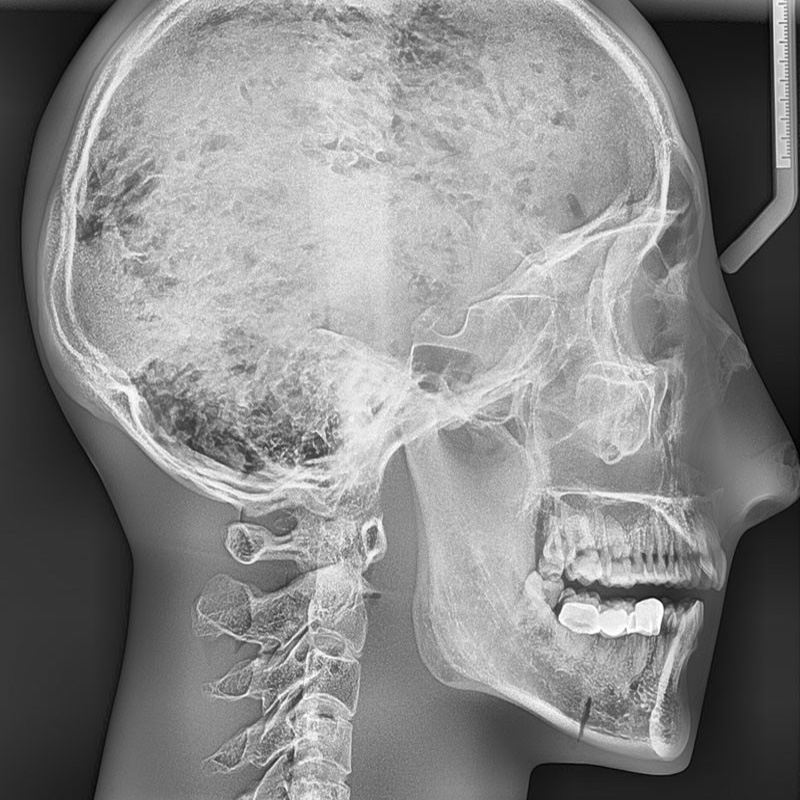

1. 模型包含具有天然齒列的真實人類頜骨和5-7截頸椎,整體包埋于軟組織等效材料中

2. 頭骨是醫(yī)學教學用頭骨,沒有降解跡象

3. 牙齒為未脫落的天然牙齒,部分牙齒有牙科修復痕跡。

4. 模式可顯示完整的頭部骨骼解剖結構,但是沒有軟組織或軟骨解剖,沒有氣管

人類頭蓋骨與下頜骨及五節(jié)頸椎

頭骨與下頜骨及不含頸椎